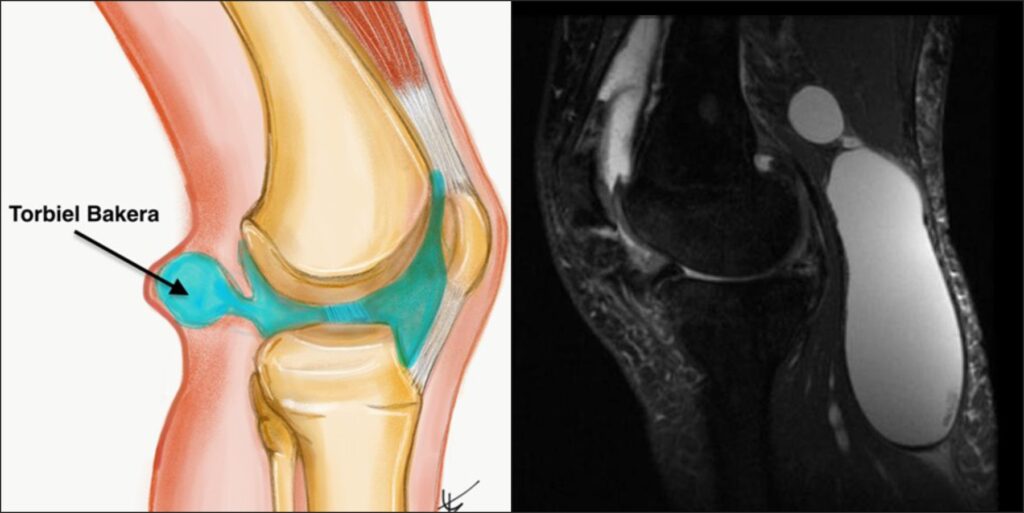

Jak się leczy cystę Bakera

Jak się leczy cystę Bakera?   Cysta Bakera, znana również jako torbiel podkolanowa (ang. popliteal cyst), to dość częste schorzenie stawu kolanowego. Bywa powodem niepokoju pacjentów z racji pojawienia się miękkiego guza w dole podkolanowym. U dorosłych pacjentów najczęściej występuje wtórnie do chorób zwyrodnieniowych i stanów zapalnych stawu kolanowego. Przedstawię aktualny stan wiedzy dotyczący etiologii,…